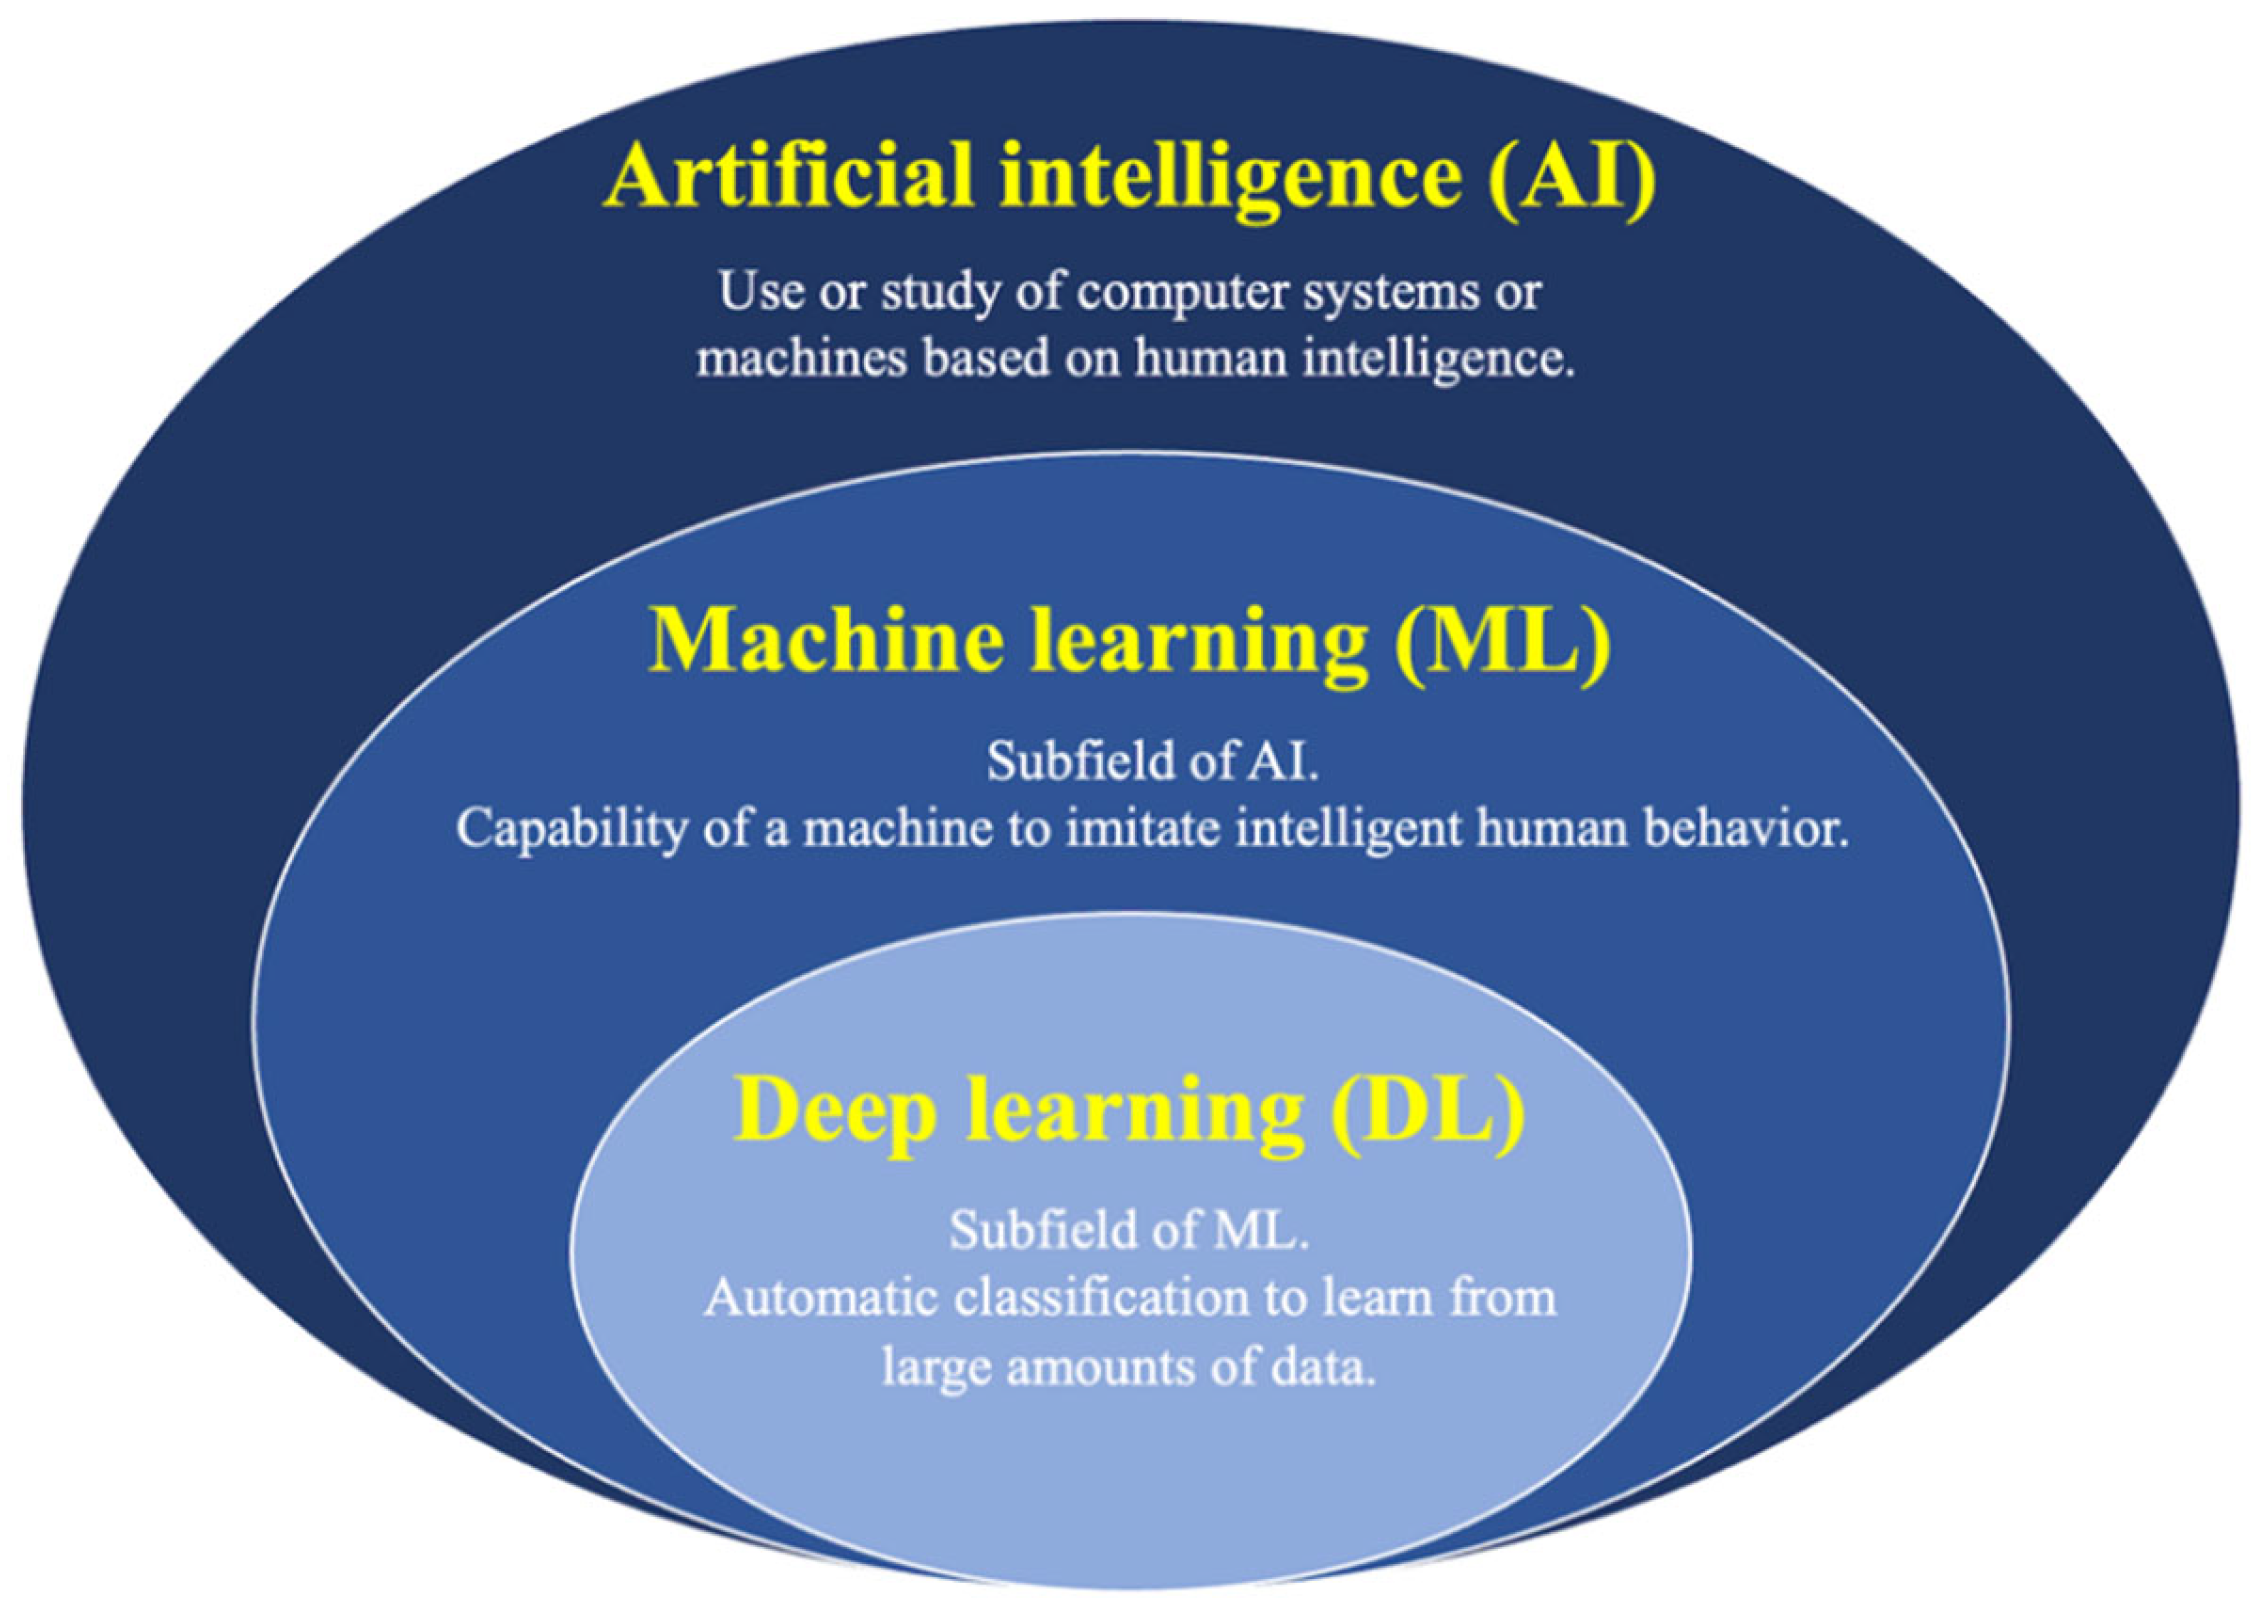

7. AI Approach to the Diagnosis of GB Lesions